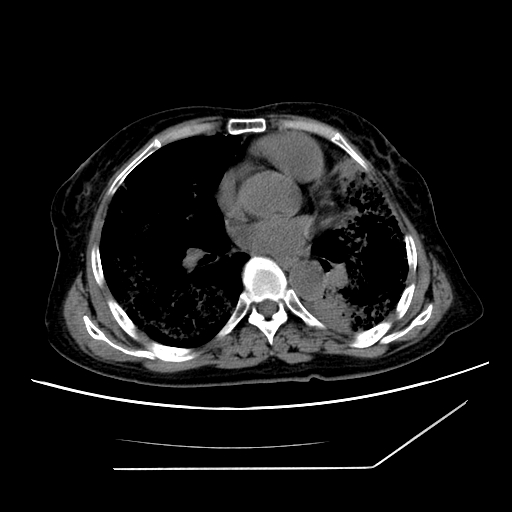

标题: CT25393:病人45岁,咳嗽,吐黄痰带血丝,发热,胸闷月余 [打印本页]

标题: CT25393:病人45岁,咳嗽,吐黄痰带血丝,发热,胸闷月余

1、左肺中央型肺癌并双肺弥漫性转移   2、双肺部感染    3、肺大泡     4、左侧胸腔积液

双侧肺弥漫性病变,可见“空泡征”及“蜂窝征”,考虑肺泡癌可能性大,左侧胸腔积液,考虑胸膜受累可能!

1)不排除肺泡癌可能。2)左侧胸腔积液。